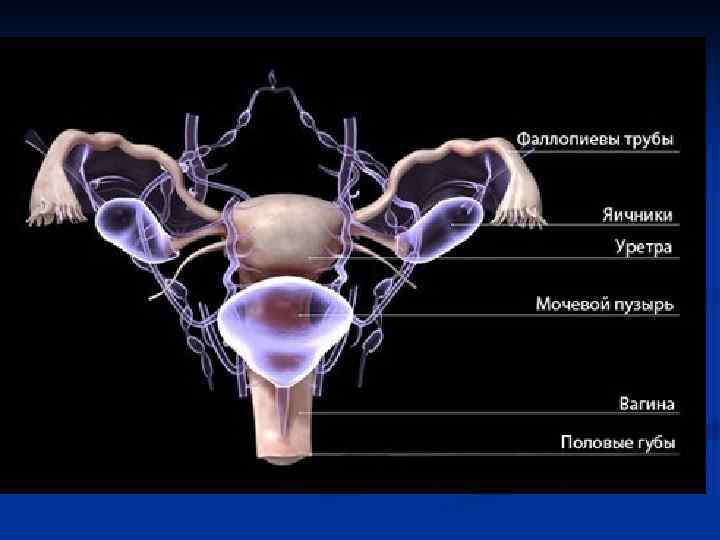

Женские половые органы, organa genitalia feminina

Женские половые органы, organa genitalia feminina